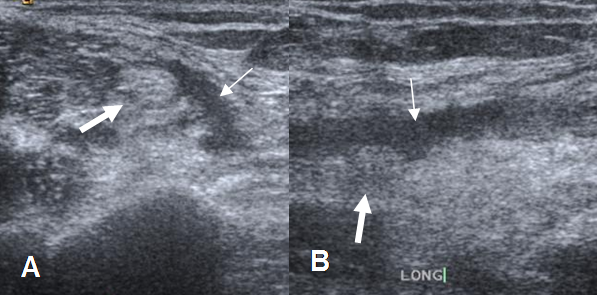

La ecografía tiene las desventajas de ser operador dependiente, su difícil reproductibilidad y la dificultad para valorar completamente el tendón, sobre todo su parte distal. Las ventajas es que permite el estudio comparativo y la exploración dinámica. (15). Con esta modalidad encontramos discontinuidad del tendón y retracción. (Fig 38 A y B).

Fig 38 A. Ruptura parcial del biceps.

A: Ecografía transversal y B: Ecografía longitudinal. Músculo biceps adelgazado y con pérdida de su patrón fibrilar (Flecha gruesa), rodeado por líquido (Flecha delgada), secundario a ruptura parcial.